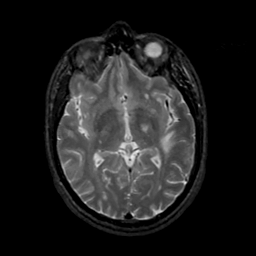

MR Study #17, July 7, 1991 -- Slice #24